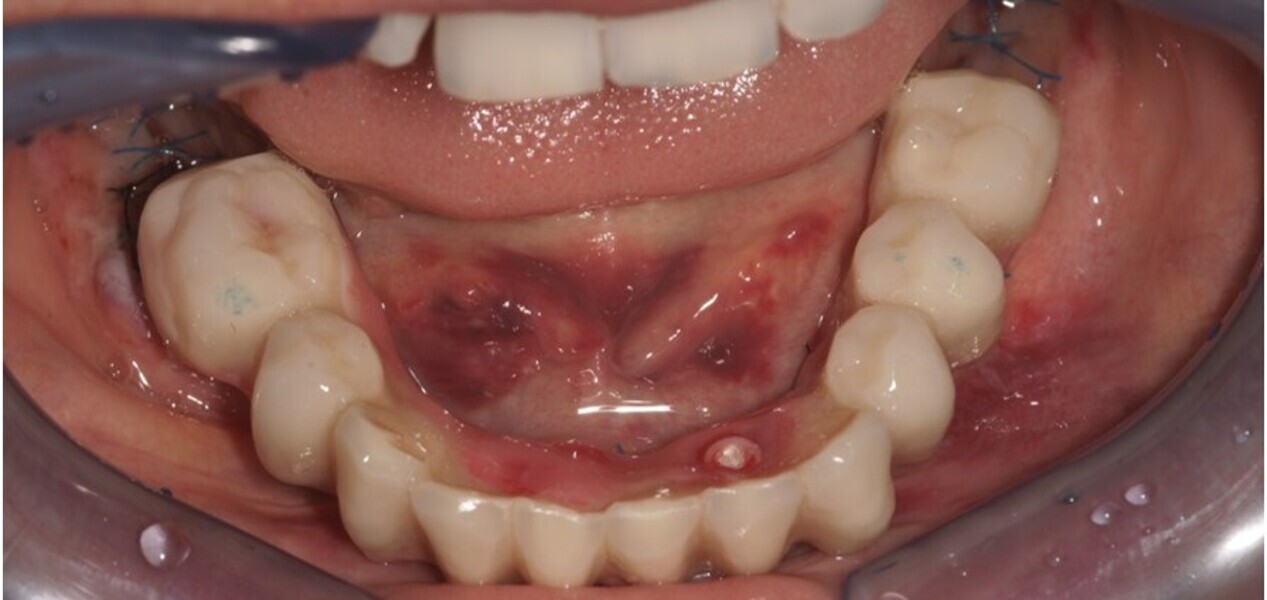

Natychmiastowa implantacja i zaopatrzenie protetyczne pacjentów z zaawansowaną chorobą przyzębia